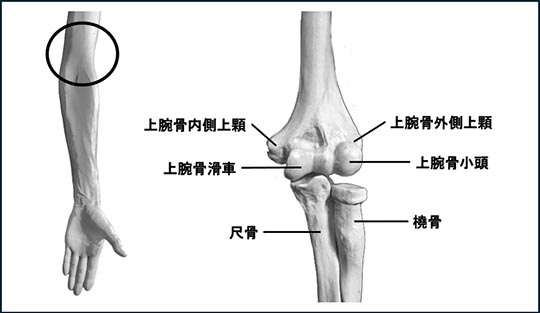

上腕骨遠位部(じょうわんこつえんいぶ)は、上腕骨内側上顆(〜ないそくじょうか)、上腕骨外側上顆(〜がいそくじょうか)、上腕骨滑車(〜かっしゃ)と上腕骨小頭(〜しょうとう)から成ります。前腕の橈骨(とうこつ)と尺骨(しゃっこつ)と共に肘関節を構成しています。上腕骨遠位部骨折は肘の周辺で起こる骨折です(図1)。

図1.肘関節:親指側が「上腕骨外側上顆」、小指側が「上腕骨内側上顆」です。